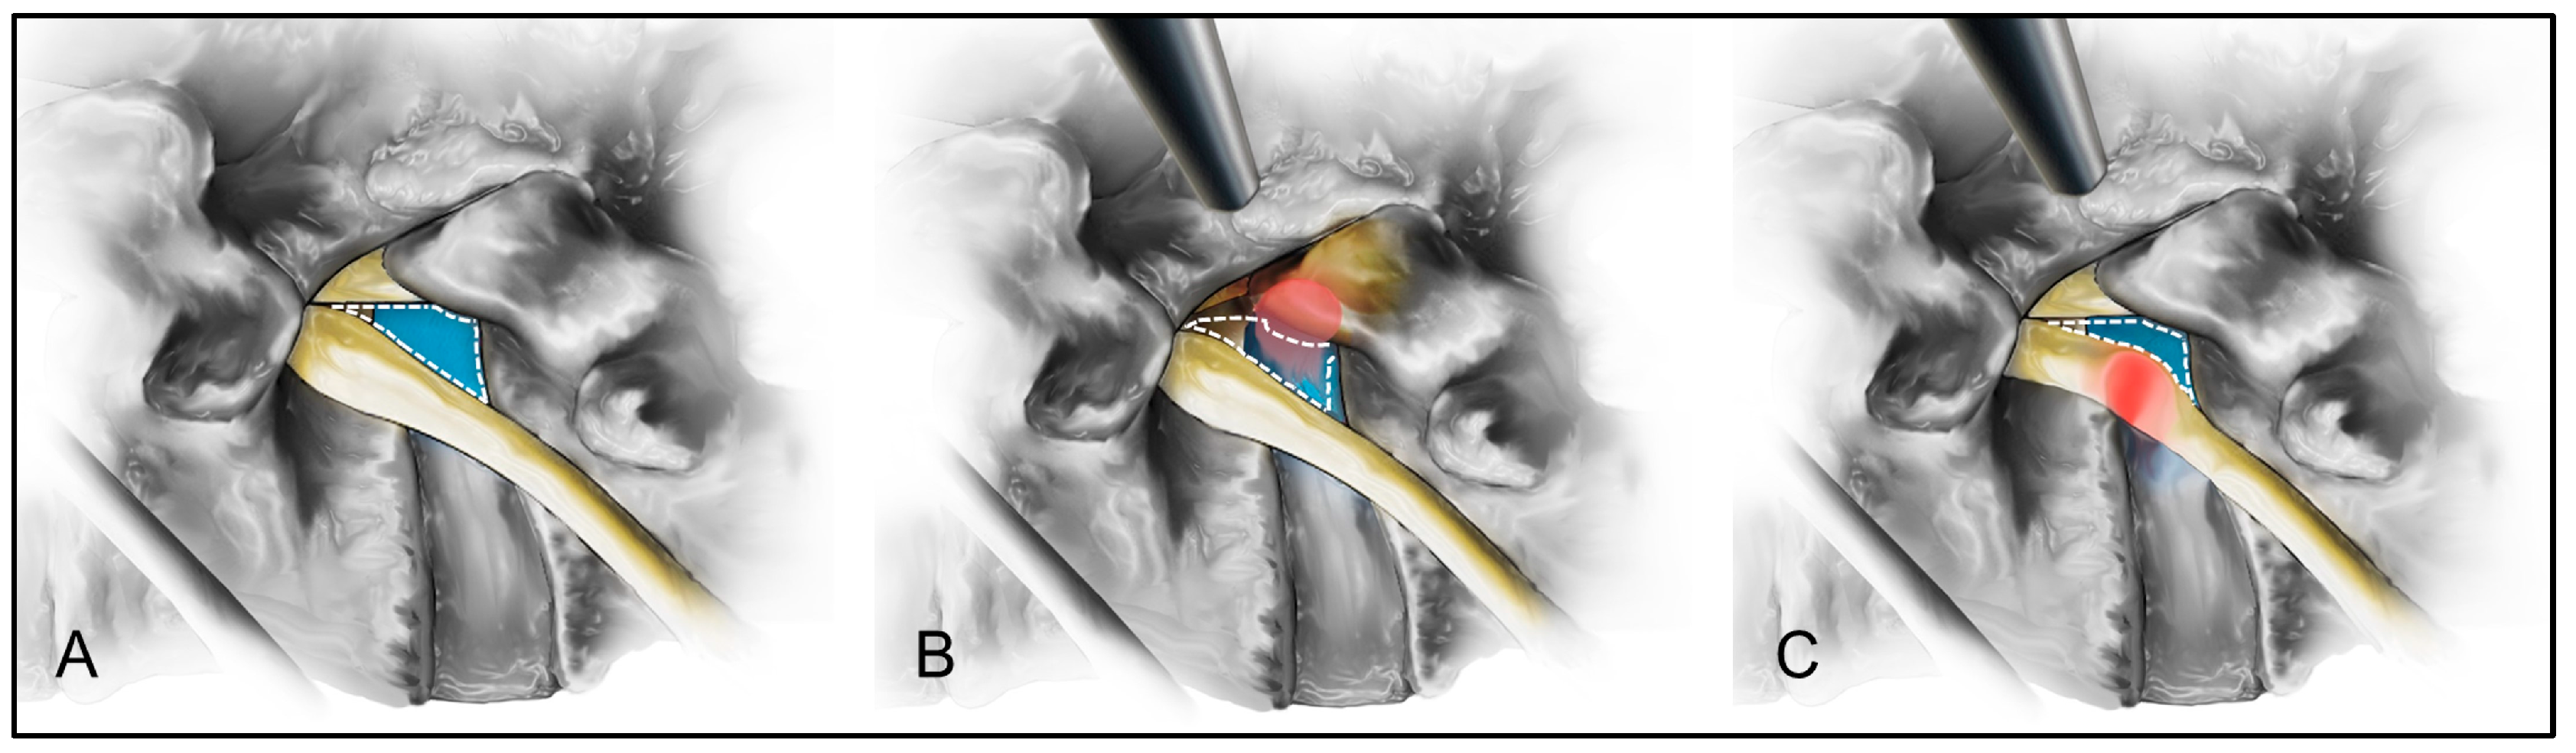

2.3. Surgical Technique

4.4. Inherent Difficulties of the Transforaminal Endoscopic Approach

4.5. Strategies to Reduce Access Pain and Operative Time